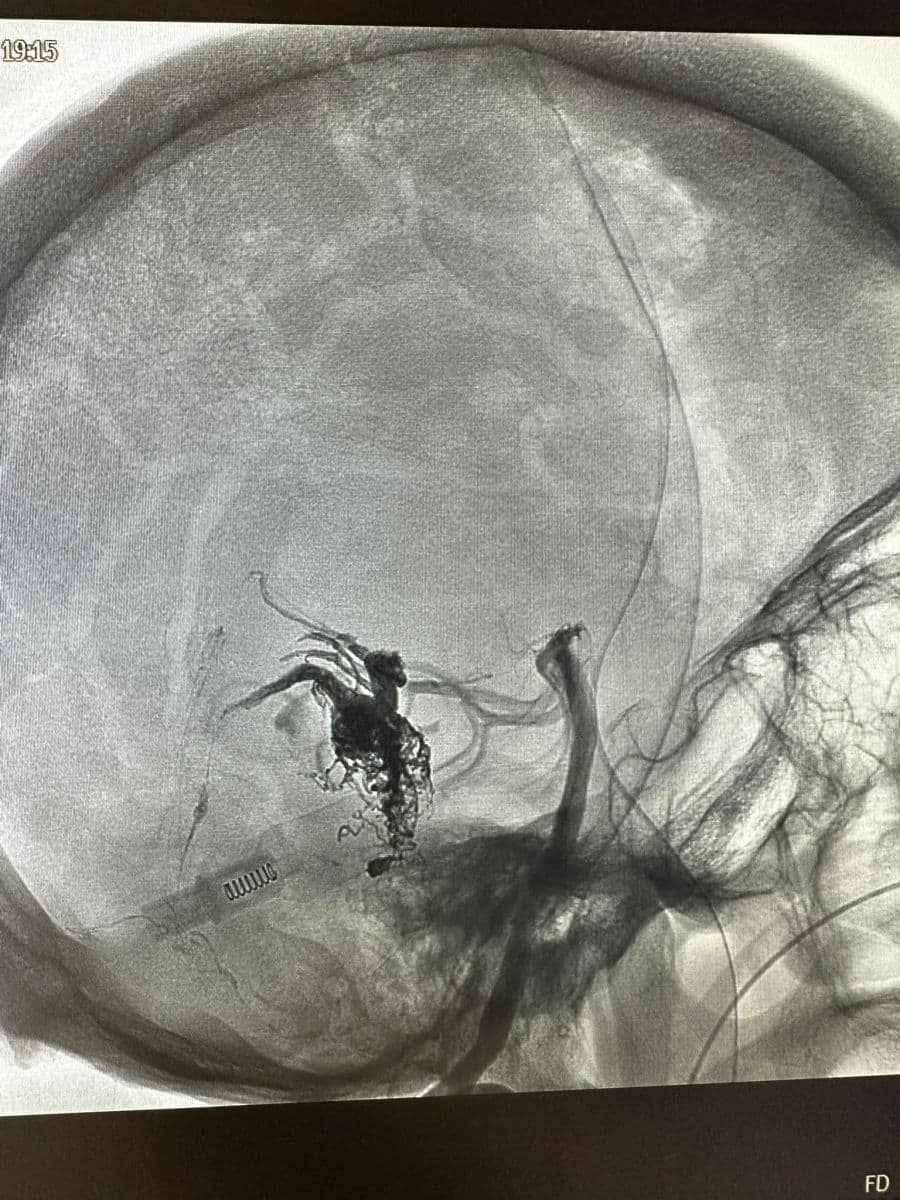

Δια ζώσης συμμετοχή των φοιτητών του Πανεπιστημίου Πατρών σε εξειδικευμένες τεχνικές ενδοαγγειακής αντιμετώπισης αγγειακών δυσπλασιών του κεντρικού νευρικού συστήματος.

Στην επέμβαση συμμετείχαν ο Καθηγητής Ενδοαγγειακής Νευροχειρουργικής Κος Β. Παναγιωτόπουλος, ο Καθηγητής Επεμβατικής Νευροακτινολογίας κος Π. Ζαμπάκης, ο επιμελητής επεμβατικής ακτινολογίας κος Μ. Θεοφάνης και ο αναισθησιολόγος κ. Γούδας.